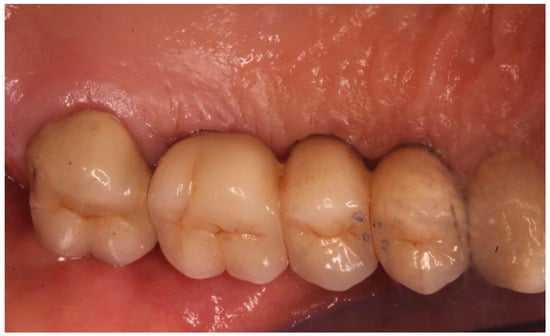

2. Materials and Methods

2.4. Tomographic Examination

3.4. Cone-Beam Computed Tomography Assessment